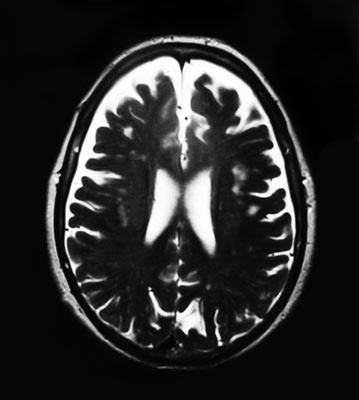

Знание таких закономерностей позволяет предположить, какие именно проблемы испытывает пациент. Получив результаты МРТ, я отправляю пациента на нейропсихологическое тестирование (исследование сохранности отдельных функций мозга), потом провожу с ним беседу и слушаю, как он говорит, и лишь после этого выдаю свои рекомендации.

Но поймите меня правильно: если какая-то область мозга истощена, это еще не означает снижение функции, за которую эта область отвечает. Нужно обязательно учитывать индивидуальные особенности мозга. Когда речь идет о мозге, чаще всего трудно окончательно установить, что является причиной проблем пациента.

Но обследование помогает понять, например, почему пациент постоянно совершает одни и те же промахи.

Обследование сосудов мозга с помощью МРА помогает понять, какие функции ослаблены и какие почти не задействованы, если с помощью МРТ этого выяснить не удалось. В участки, которые часто используются, должно поступать много кислорода и глюкозы, а для этого нужны развитые сосуды. А в почти бездействующие зоны нет необходимости доставлять кислород и глюкозу, поэтому сосуды там слабее. Так можно выяснить, что у пациента получается плохо или что он не привык делать.

Однако и в этом случае нельзя утверждать, что сосуды ослабли, потому что какие-либо функции мозга не использовались. Возможно, сначала по какой-то причине ухудшилось состояние сосудов, а уже из-за этого снизилась активность функций, за которые отвечает данная зона.

Например, если в одном из участков мозга возникает дефект под названием лимфатическая мальформация, то поступление крови туда затрудняется. В некоторых случаях при этом ухудшается память и появляются проблемы с плавностью речи. В такой ситуации будет сложно добиться изменений к лучшему, сколько упражнений ни делай. Придется признать наличие физического дефекта и восполнять недостатки функционирования мозга. Например, чаще записывать информацию.

В случае стеноза (сужения) сосудов мозга нужно одновременно проводить лечение и тренировать сниженные функции, иначе будет невозможно устранить корень проблемы. Это еще один способ применения информации от МРА.

МРТ-снимок мозга девушки, которая жалуется на периодические головокружения. Кроме того, она не может сразу подобрать нужные слова. В правой лобной доле (если смотреть на фото так, как есть, – то слева) видна лимфатическая мальформация.